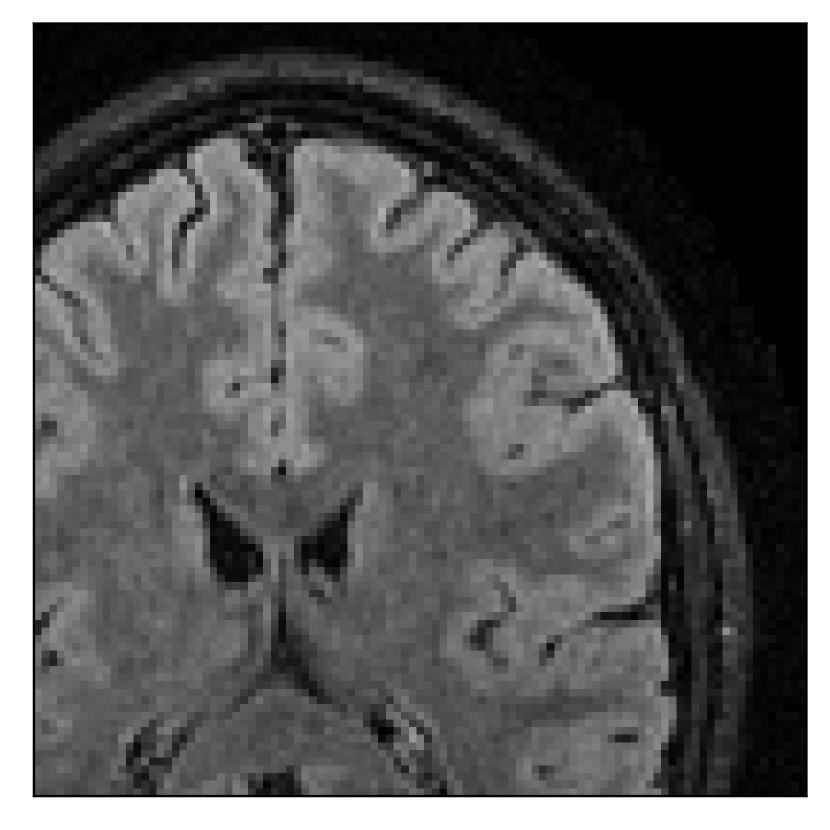

In the first experiment, we asked volunteer 3 to change position once during the prospectively-corrupted acquisition. We consider a corrupted T2-weighted contrast and a reference T1-weighted contrast (see Table 1). One important aspect of this experiment is related to the acquisition protocol of the T2-weighted contrast, based on a linear-filling pattern in -space. The corrupted data used as input for the proposed motion-correction algorithm is obtained by exporting the reconstructed volume directly from the scanner, followed by a simple Fourier transform. Note that this 3D image has been obtained by a SENSE reconstruction.

4.3 Experiment 3: scanner reconstruction vs raw k-space data

The results of the two experiments described in Section 3.3 are depicted in Figures 12 and 14. The main difference between the two experiments is related to the input data for the proposed motion-correction algorithm.

In the first experiment, the corrupted contrast has been acquired with a protocol based on a linear filling pattern in -space. Note that, in this particular case, the scanner reconstruction implements the SENSE method. We then extracted the DICOM of both amplitude and phase produced by the scanner, and used it as input data (after a Fourier transform) for the algorithm. The proposed scheme is able to successfully remove the motion artifacts in Figure 12.